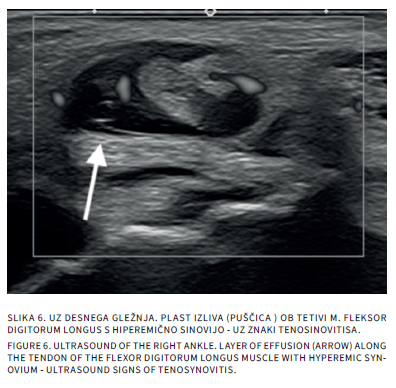

Bolečine v mišičnoskeletnem sistemu so v otroškem obdobju sorazmerno pogoste. Delimo jih na akutne in kronične, slednje trajajo več kot 3 mesece. Diferencialna diagnoza tako akutnih kot kroničnih bolečin v sklepih pri otrocih je široka. Slikovne preiskave so poleg anamneze, klinične slike in laboratorijskih izvidov pomembne v diagnostičnem postopku iskanja vzrokov bolečine. Katero slikovno metodo uporabimo najprej, je odvisno od mesta bolečine in od prizadetosti tkiva. Pri mehkotkivnih spremembah in oteklinah sklepov je prva diagnostična metoda ultrazvočna preiskava, pri sumu na prizadetost kosti pa rentgensko slikanje. Če je potrebno, sledi magnetnoresonančno slikanje ali računalniška tomografija. V prispevku bomo opisali anatomske in morfološke značilnosti otroškega skeleta, ki lahko dajejo videz patoloških sprememb ter slikovne diagnostične postopke pri akutnih in kroničnih bolečinah v sklepih.